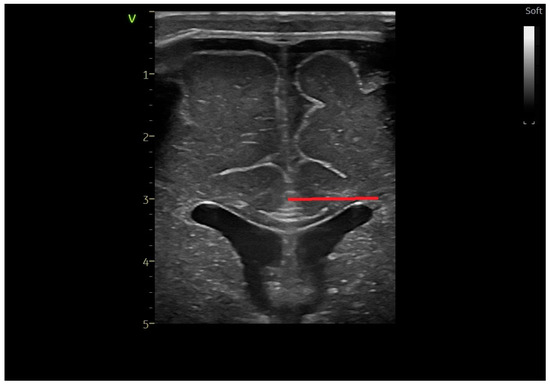

2.2. Head Ultrasound Measurements at TEA